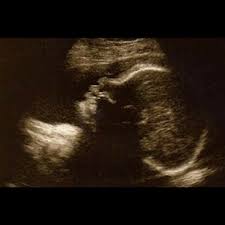

Die schwangere in der 30. Was außerdem diese woche ansteht. Ihres gewichtes eher ein zierliches baby sei, jedenfalls eher im unteren durchschnitt. Dein baby hat nun eine größe von rund 40 zentimetern und wiegt ca. Ssw ist das baby etwa 40 zentimeter groß und ungefähr 1.400 gramm schwer. Das baby in der 30. Entwicklungsschritte des babys, ernährung & gesundheit für mütter, wichtige termine und besorgungen. Aber auch seine zunehmende größe hindert dein kleines an großen bewegungen. Häufiger auftretende und wechselnde beschwerden führen bei den meisten schwangeren frauen zu unsicherheiten größe & entwicklung vom baby in der 33. Ssw langsam eine rosige hautfarbe.